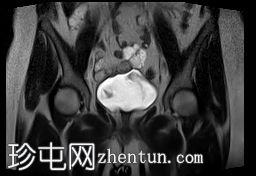

矢状位

T2加权像

MRI特征符合剖宫产术后瘢痕子宫内膜异位症,表现为特征性T1高信号伴T1FS持续存在,T2低信号伴内部高信号灶,病灶边缘浸润于腹前壁肌肉内,以及对比增强。

该病灶累及腹白线并浸润腹直肌,主要位于中线左侧,耻骨联合及结节处腹直肌起点上方。

影像学表现符合病灶内出血成分,提示既往剖宫产瘢痕处存在异位子宫内膜组织。

子宫可见剖宫产瘢痕灶。